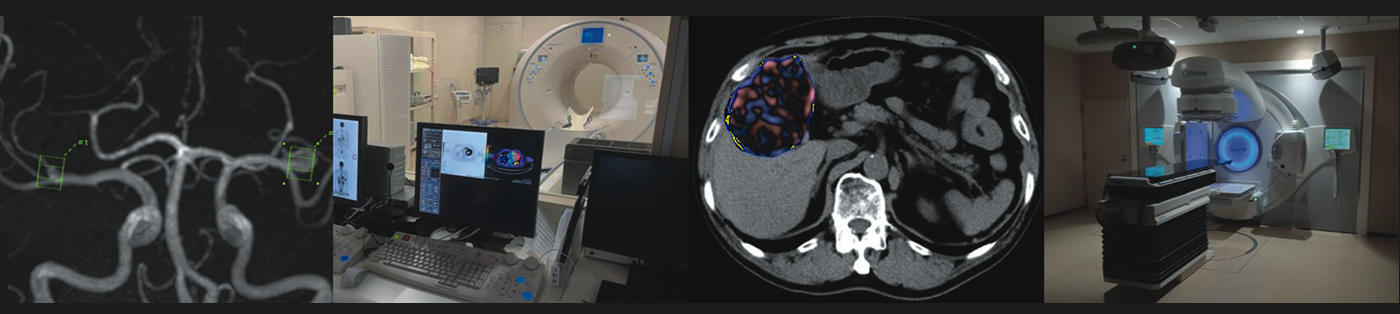

国際医療福祉大学 医学部 放射線医学教室は2017年4月に本学医学部設置とともに開設されました。本教室は診断、核医学、治療からなり、教育、診療、研究に従事しています。

本学の放射線教室の特徴として本学医学部に近隣する千葉県の国際医療福祉大学成田病院、本学本院である栃木県の国際医療福祉大学病院、東京都の国際医療福祉大学三田病院、医療法人財団 順和会 山王病院、山王メディカルセンター、赤坂山王メディカルセンター、静岡県の国際医療福祉大学熱海病院にそれぞれ放射線科医が在籍、総勢約30名の放射線科医がネットワークで接続されたシステムを用いて高い連携のもとに診療を行っています。専門性に応じて医学生や研修医を教育、また施設間にて共同で研究を行っています。診療の必要により各施設のデータにアクセスしやすい環境が実現されています。

本学の理念の一つである国際性は本教室の重要なキーワードになります。海外と共同での業務を行い、海外から認知される研究の推進を推奨しています。多様性も重視しており、働きやすい環境を実現しています。また、本教室は学閥がないのが特徴で、国内の様々な施設からの教育者・研究者を受け入れています。放射線医学そのものがmultidisciplinaryな開発・研究で進歩してきた背景があり、医学にかかわらず様々なサイエンスの分野とのコラボレーションを目指しています。

放射線医学は発展が目覚ましい領域で最新の知見やテクノロジーの洗礼をうけてきました。最近ではディープラーニングを筆頭とした人工知能がこれに相当します。これらに対応して医療に役立てるためには常に柔軟な発想や考え方が必要とされますが、開設間もない教室である本教室には新しい時代に対応した体制を築きやすいという強みがあります。これからの歴史を一緒につくってくれる方々をいつでも歓迎します。